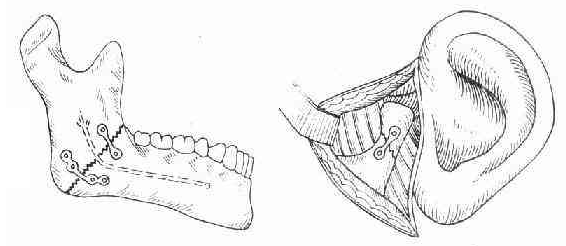

切开复位和内固定

(1)下颌小型板系统固定下颌骨颏部、下颌体以及下颌角单发骨折:小型板固定为单层皮质骨固定,不会损伤下齿槽管,而且板易弯制成形,并按张应力轨迹放置。 (2)下颌骨骨折拉力螺钉固定:拉力螺钉固定是以最小的植入体获得最大的稳定性。临床主要用于下颌体斜断面骨折、颏部骨折、下颌角垂直断面骨折、髁颈下骨折和游离骨折块固定。 (3)发生于颏/颏旁及下颌体的广泛的粉碎性骨折:重建接骨板主要用于连接骨折区两侧的骨段,骨折区内的小骨片可以用小型或微型接骨板连接,也可以直接用螺钉做穿接固定。 骨折线上牙的处理 保留骨折线上的牙齿除了可以有效的帮助骨折的复位和固定,防止骨折段的错位,还有利于牙弓外形的正确恢复。拔出骨折线上可以保留的牙齿可以造成骨组织的损伤、干扰正确的复位和固定。除影响复位的下颌智齿、有明显感染的牙齿以及牙颈部以下折断的牙齿,应尽量保留骨折线上的牙齿,以利于骨折的复位固定和后期的咬合重建。 无牙下颌骨骨折的治疗 无牙的下颌骨骨折的处理较为困难,首先无牙可供作简便的颌间固定;同时由于长期缺牙可致牙槽骨萎缩,下颌体部变得细小,骨折时受肌肉的牵拉,骨折段更易于移位。对于年龄较大有全身系统性疾病的患者,可以利用原有的上下颌全口托牙或塑料牙托夹板作颌周栓丝结扎固定,但稳定制动不可靠,甚至可以引起软组织的压迫性坏死。移位明显的无牙下颌骨骨折,在全身情况容许的情况下,一般均应作开放复位内固定,应选择固位力较强的板钉系统进行固定。